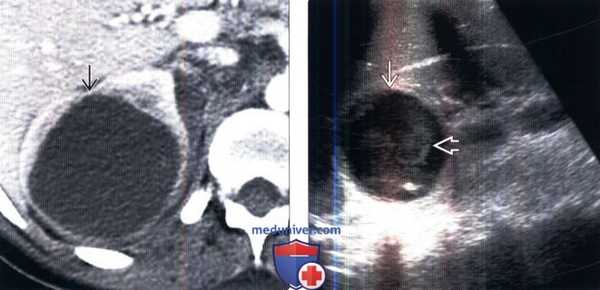

(Слева) КТ правой почки с контрастированием, аксиальная проекция: выявлено крупное образование в почке, не накапливающее контраст и окруженное капсулой с плотностью 20 HU (предположительно абсцесс).

(Справа) УЗИ правой почки в сагиттальной плоскости: у того же пациента выявлено округлое анэхогенное образование с низкоуровневыми внутренними эхо-сигналами и задним акустическим усилением. Лихорадка в анамнезе и данные визуализации указывают на наличие абсцесса.